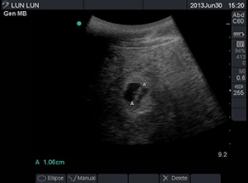

2013-07-08从美国亚特兰大动物园7月1日(美国时间)新闻发布会获悉:超声波和激素检查均表明,今年15岁的成都旅美大熊猫“伦伦”已成功怀孕,小宝宝或将于本月诞生。图/文 杨菲菲 许萍1017